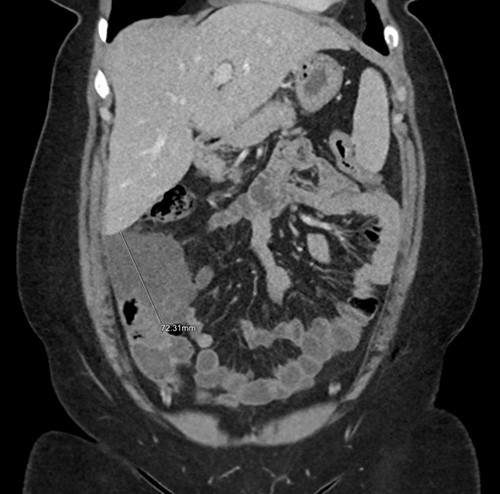

The white cell count was 10.5 × 109/l, C-reactive protein 6.8 mg/l, B-hCG negative, urine culture negative. Ultrasound (US) abdomen did not identify the appendix or the right ovary but noted a 102 × 43 × 52 mm complex multi-locular cyst. Computed tomography (CT) abdomen showed a focal low-density mass with adjacent inflammatory change anterior to the ascending colon measuring 43 × 55 × 54 mm (Figs 1–3). This mass appeared separate to the ovary and the appendix.

Coronal CT reconstruction measuring the largest dimension of mass.